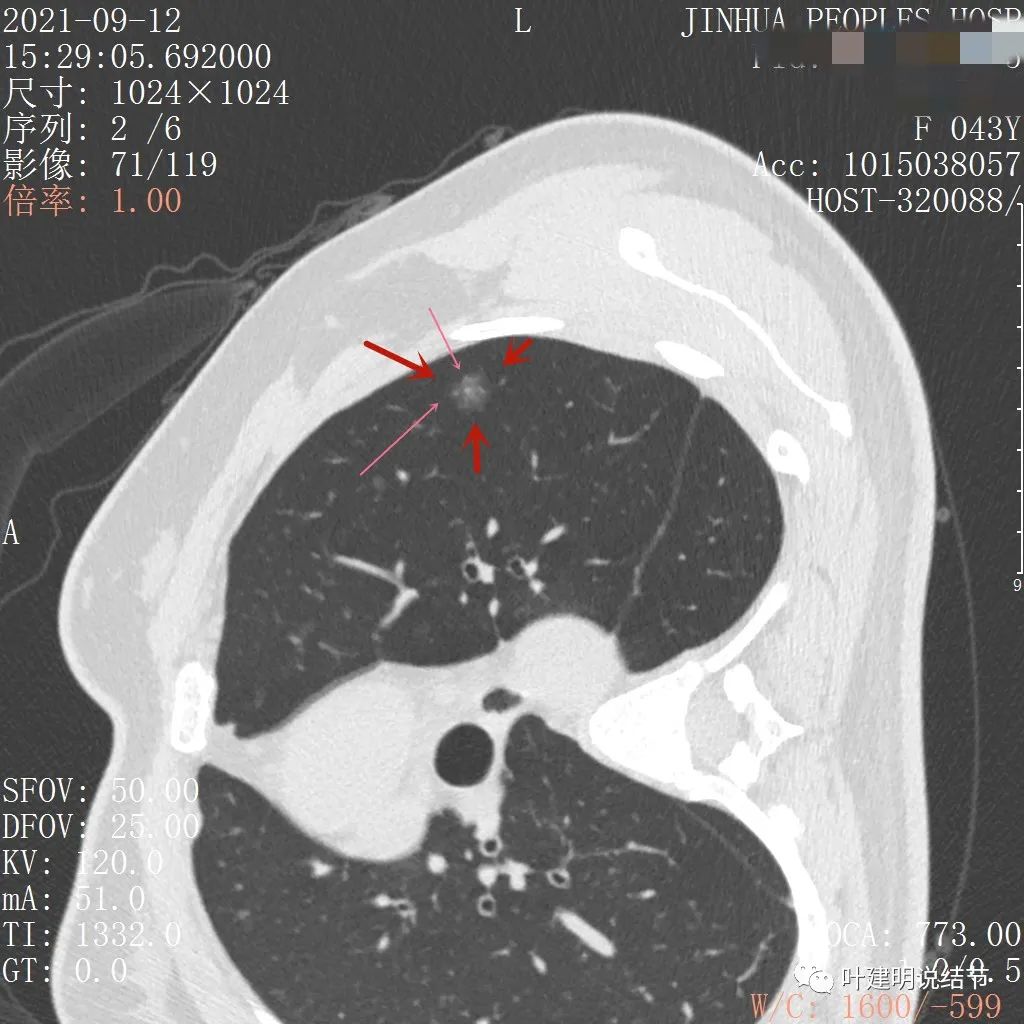

不均质的偏低密度磨玻璃结节,轮廓清

上图示病灶内部有高密度点状成分(粉色箭头所指)

同样示内部点状高密度,瘤肺边界清,密度显乱

上图显示混合磨玻璃结节,中间点状高密度区域,边上有微小血管征